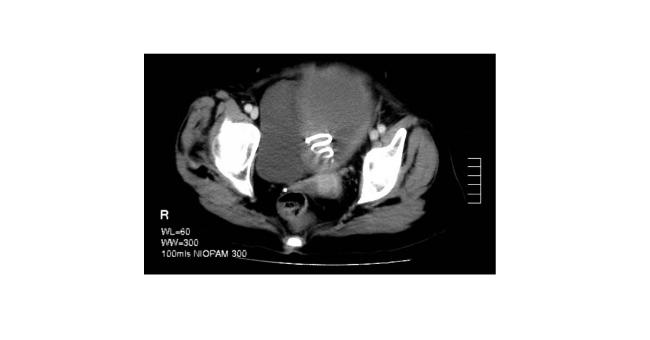

A 66 year old Caucasian, post-menopausal woman was admitted to hospital under the care of the general physicians. She had a three months history of cough and productive green sputum, weight loss, poor appetite and frequent night sweats. Interestingly there was no history of vaginal bleeding. Examination Clinical examination revealed she was febrile